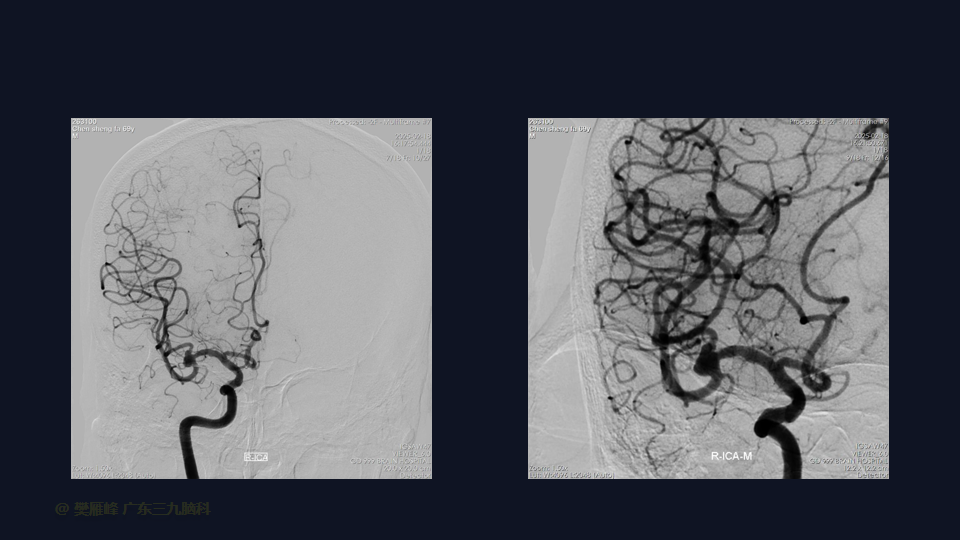

我们介绍一名69岁男性病例,他因反复头晕2个月发现的一个大型、宽颈、未破裂的MCA复杂性动脉瘤。由于动脉瘤的形态、位置和破裂风险,选择了显微外科夹闭。进行了右侧翼点入路,患者外侧裂较难分离。手术视频重点介绍了关键步骤,如分离复杂外侧裂、去除额叶粘连、实现近端和远端控制,以及在临时阻断下夹闭。夹闭后血管造影确认分岔重建良好,动脉瘤完全消失,MCA循环得以保留。术后患者神经功能完好,于术后第 10天出院。本病例强调了针对复杂MCA动脉瘤量身选择适当的动脉瘤夹重建的重要性,采用精细的侧裂分离技术和细致的动脉瘤颈剥离技术。显微外科夹闭仍是处理大型复杂MCA动脉瘤的首选方法,尽管存在固有风险,但具有高闭塞率和实用性。

在这段手术视频中,展示了一名69岁男性的病例,他因反复头晕2个月发现的大脑中动脉动脉瘤